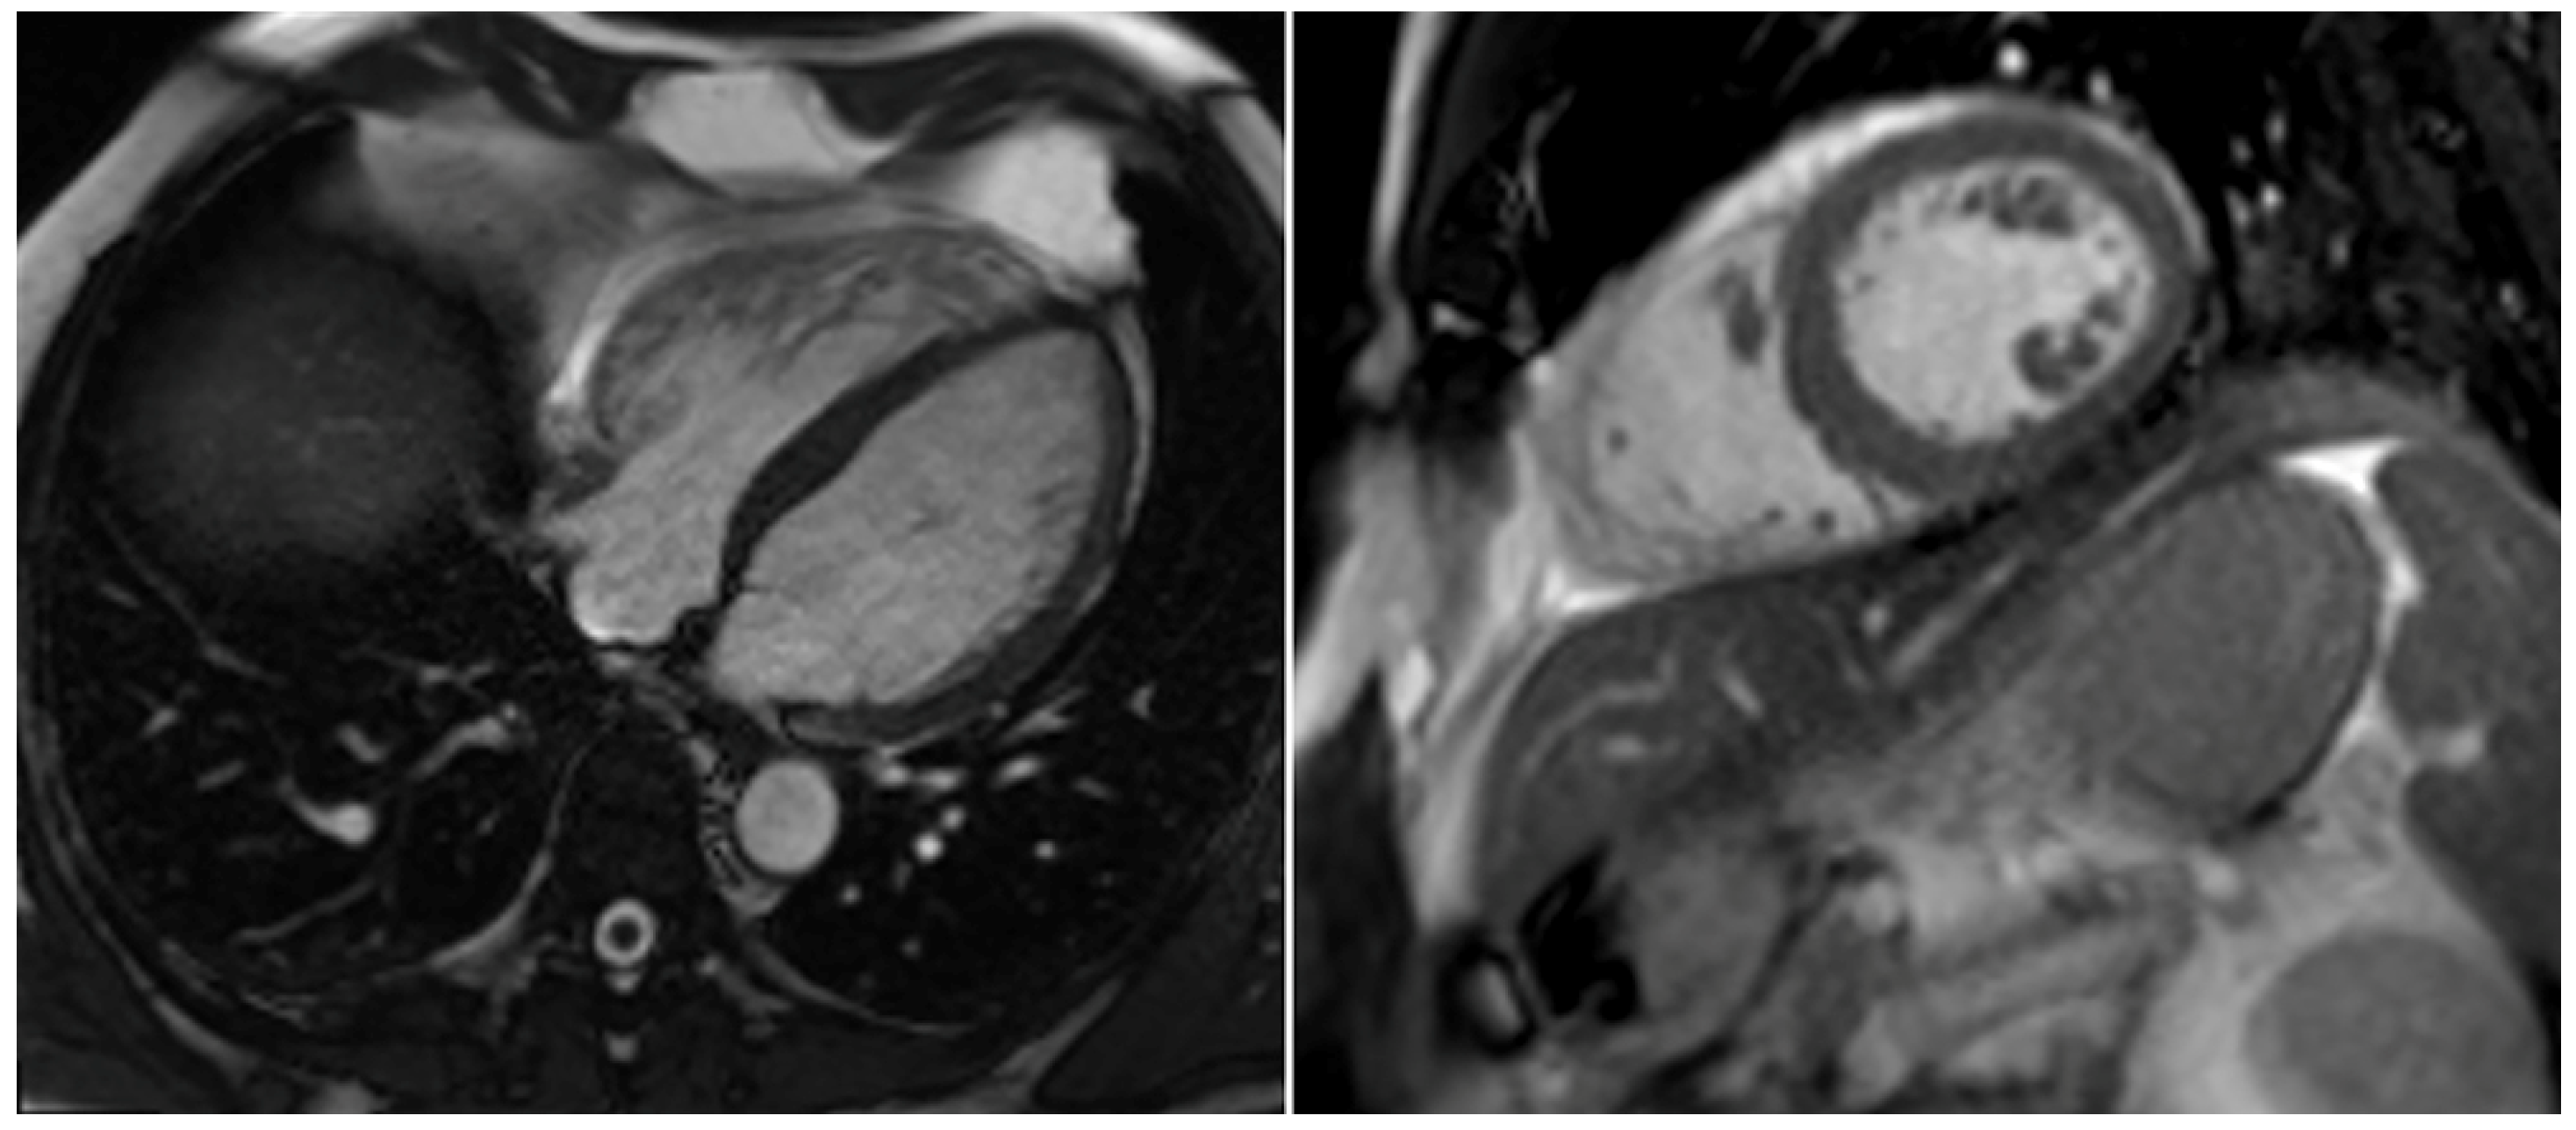

2. Case Report

| RVEDD [mm] | 65 | 49 | 37 |

| TAPSE [mm] | 12 | 16 | 21 |

| TASV [cm/s] | 8 | 12 | 17 |

| sPAP [mmHg] | 55 | 15 | 14 |

| LVEF [%] | 43 | 54 | 56 |

| D- Sign | Yes | No | No |

| McConnell‘s sign | Yes | Yes | No |

| Systolic notching of PWD over pulmonary valve | Yes | Slightly | No |